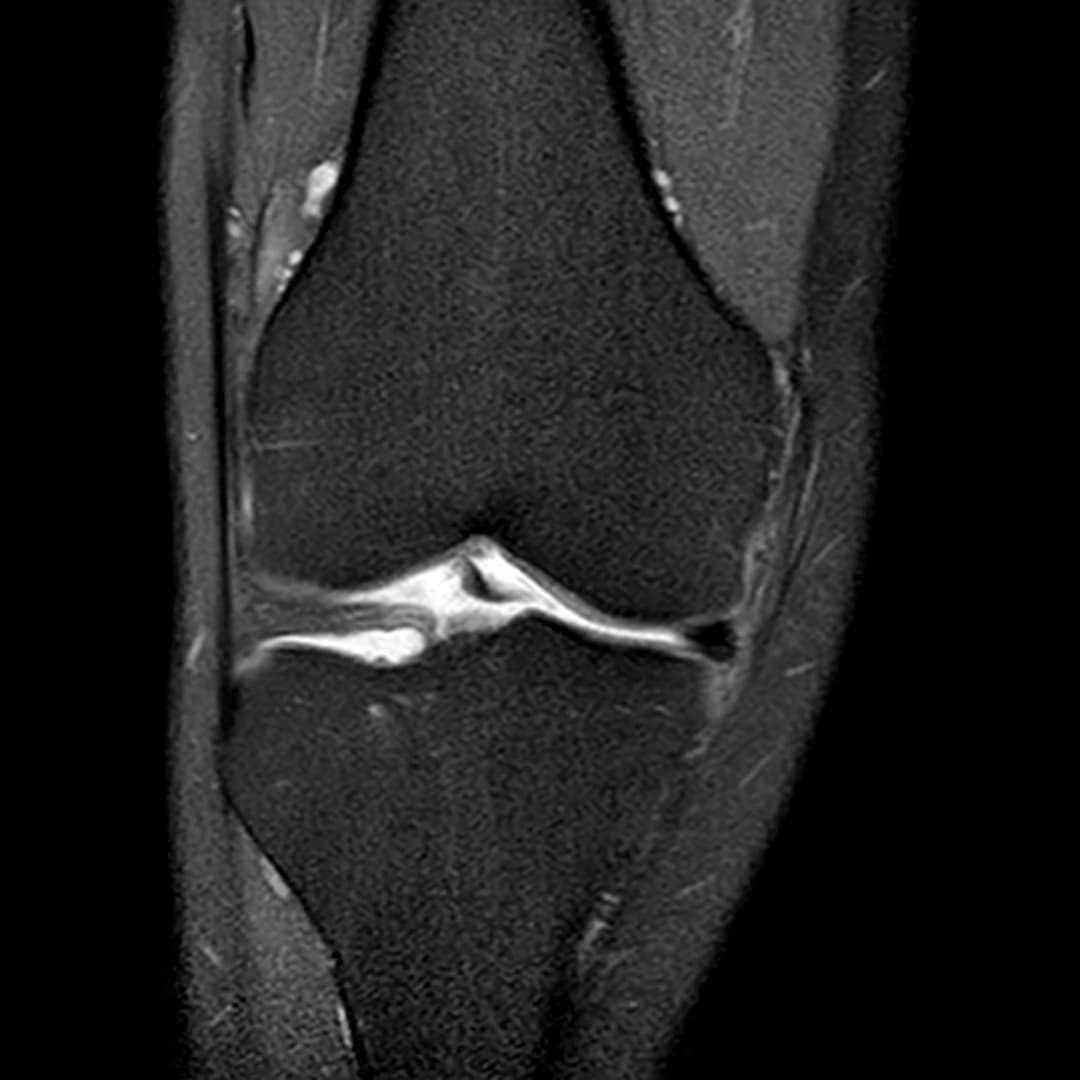

Fissure de grade 3 du segment moyen du ménisque médial.

Languette méniscale rattachée à la corne antérieure du ménisque médial avec aspect flottant sur le versant antérieur de l'échancrure.